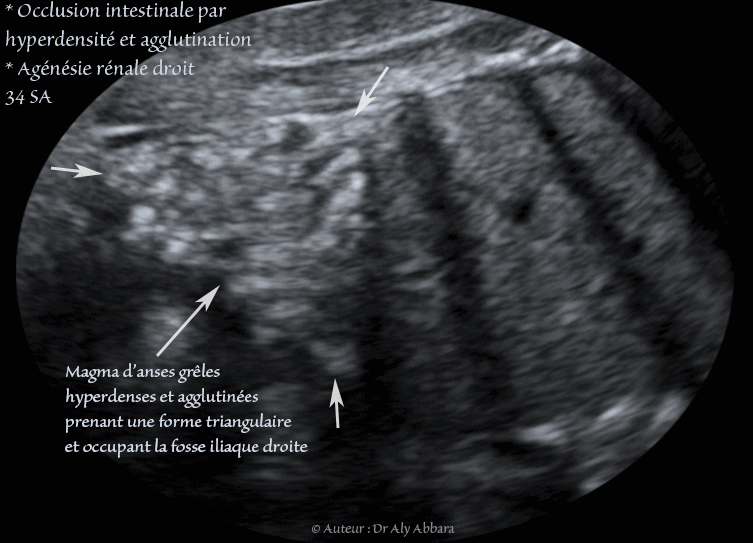

Cette occlusion intestinale est liée à la présence, dans la fosse iliaque droite, comme on le voit sur ces images, d'un magma d'anses grêles hyperdenses, agglutinées et obstruées.

Ce magma digestif intestinal prend une forme triangulaire (pyramidale) sur la coupe frontale de l'abdomen centrée sur la fosse iliaque droite